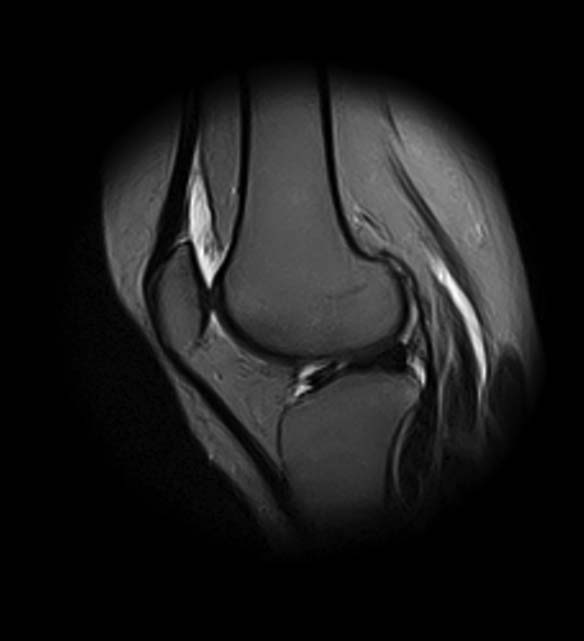

добрый день! Не очень понятен принцип, по которому отбирались снимки МРТ. Большинство из них не показательны. Вижу пока только повреждение хряща на феморопателлярной поверхности. Хлтелось бы посмотреть диск целиком

На снимках повреждений наружного мениска не вижу и кисты мениска не вижу. Есть повреждение хряща на передней поверхности внутреннего мыщелка бедра. Вполне может оказаться, что повреждение лоскутное. А какая консервативная терапия проводилась?